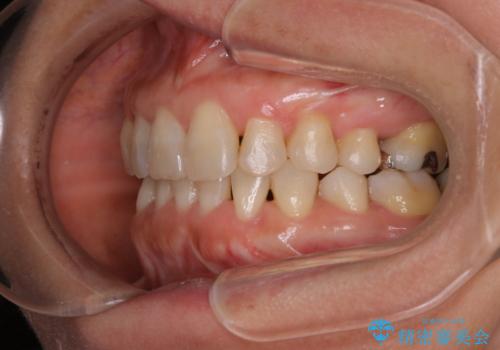

- 上下の歯のがたつきと、噛み合わせが深いことを気にされてご相談にいらした方です。噛み合わせに参加していない歯を抜歯してインビザラインにて治療を行いました。

一般的に噛み合わせの深い方へのインビザライン治療は適応が難しいとされていますが、今回は噛む力を上手にコントロールできたことと、内側に入り込んでいた前歯の角度を調整したことで下の歯がしっかり見えるようになりました。短期間で劇的に見た目が改善し、大変喜んでいただけました。